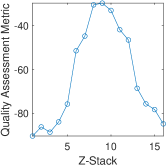

To generate a “subjective-like” score for FocusPath database, we assigned a “focus level” for each image that is determined by the difference between the best camera position and the position of interest . In other words, the score represents how far the camera is away from its best focus level when scanning a certain image slide. Specifically, every 16 images of the same content but different blur levels have a common and every image has a corresponding . A sample set of 16 images is shown in Figure 5. The value among every 16 images is determined by the proposed non-reference sharpness assessment metric in this paper. Since is found among 16 different slices of the same tissue content, the scores will guarantee to obtain the best focus level. The plot of focus level scores across 16 images is shown in Figure 6. The mathematical representation of the focus level for sharpness scoring is defined by